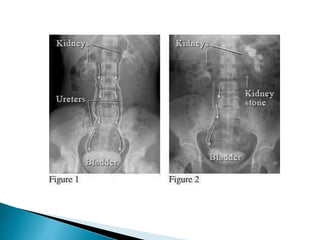

•X-ray KUB

X-RAY OF KIDNEYS,URETERS AND BLADDER